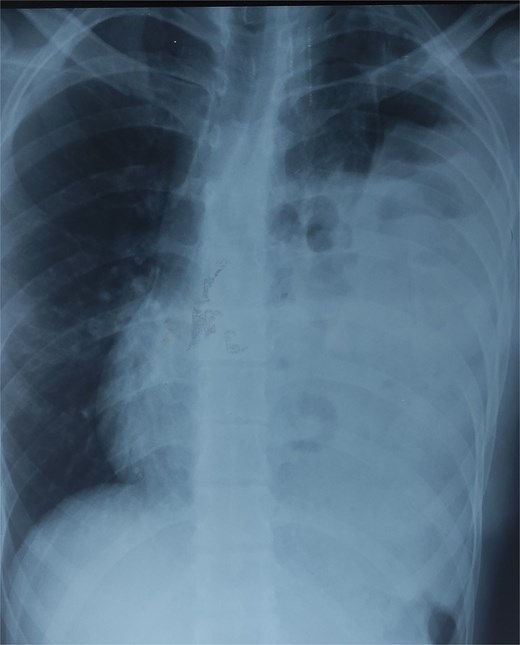

The differential diagnoses initially included pneumonia, pleural effusion, pericarditis, and hydropneumothorax. Electrocardiogram was normal. Chest X-ray revealed air-filled bowel loops in the left hemithorax (Fig. 1). A contrast-enhanced computed tomography (CT) scan of the chest and abdomen confirmed a left-sided posterolateral diaphragmatic defect with herniation of omentum, small bowel loops, appendix, caecum, ascending colon, and transverse colon into the thoracic cavity. The appendix appeared thickened with surrounding fat stranding, suggesting acute appendicitis. There was also left-sided reactive pleural effusion (Fig. 2).

Chest X-ray showing air-filled bowel loops within the left hemithorax.